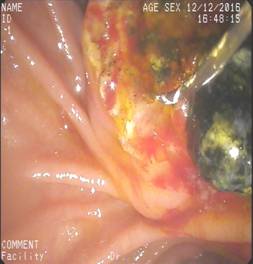

诊疗过程:因重度凝血功能障碍,予以外科手术或内镜下治疗均有发生不可控制的大出血。予以抗感染、保肝及经皮经肝胆囊穿刺引流术等保守治疗3个月,凝血功能有所好转后抓住手术时机,立即行ERCP,术中见结石嵌顿于十二指肠乳头(胆总管末端开口处),立即予以针刀切开十二指肠乳头,顺利取出胆总管结石,解除长达3个月的胆总管梗阻,术后患者很快就拔除胆囊穿刺管,恢复正常生活。

取出结石 |

取出结石后内镜下逆行胆道造影,提示胆总管全程通畅